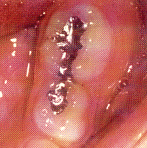

En caso de tratar las caries en dientes anteriores el profesional  elije una resina compuesta ó un ionómero vítreo, debido a que tienen excelentes propiedades estéticas. En casos de fractura dental  suele utilizarse coronas forjadas fenestradas de acero inoxidable.Ver fotos derecha.